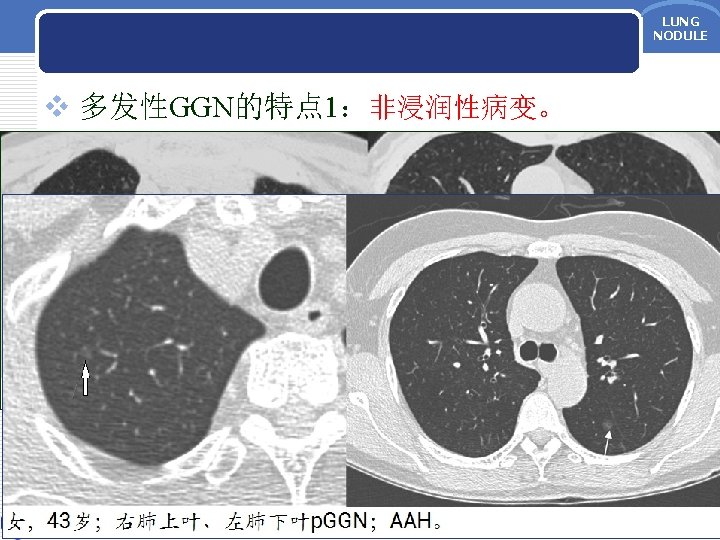

LUNG NODULE LUNG NODULE AAH p GGN 5